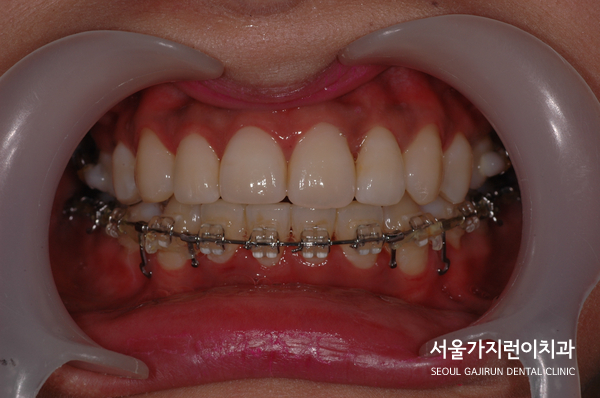

환자분이 진행한 치아교정은 설측탄댐교정방식이었는데요. 치아의 쓰러짐 없이 안정적으로 자리를 찾았고 미니스크류를 더해 정교한 컨트롤이 진행되었습니다. 사진을 보면 중심선도 맞고 뻐드러진 돌출감도 많이 해소되었는데요. 전체적인 치열이 잘 정돈된 것을 확인할 수 있었습니다.

자연스럽게 미소를 띄는 환자분! 돌출감이 심한 덧니 치아교정도 콤비교정, 설측교정으로 개선 가능하니 더 자세한 과정은 아래의 블로그를 통해 확인해보시기 바랍니다. 환자의 정밀한 상태 분석을 통해 교정노하우를 더하면 재발 걱정없이 치아교정을 마무리할 수 있겠습니다.